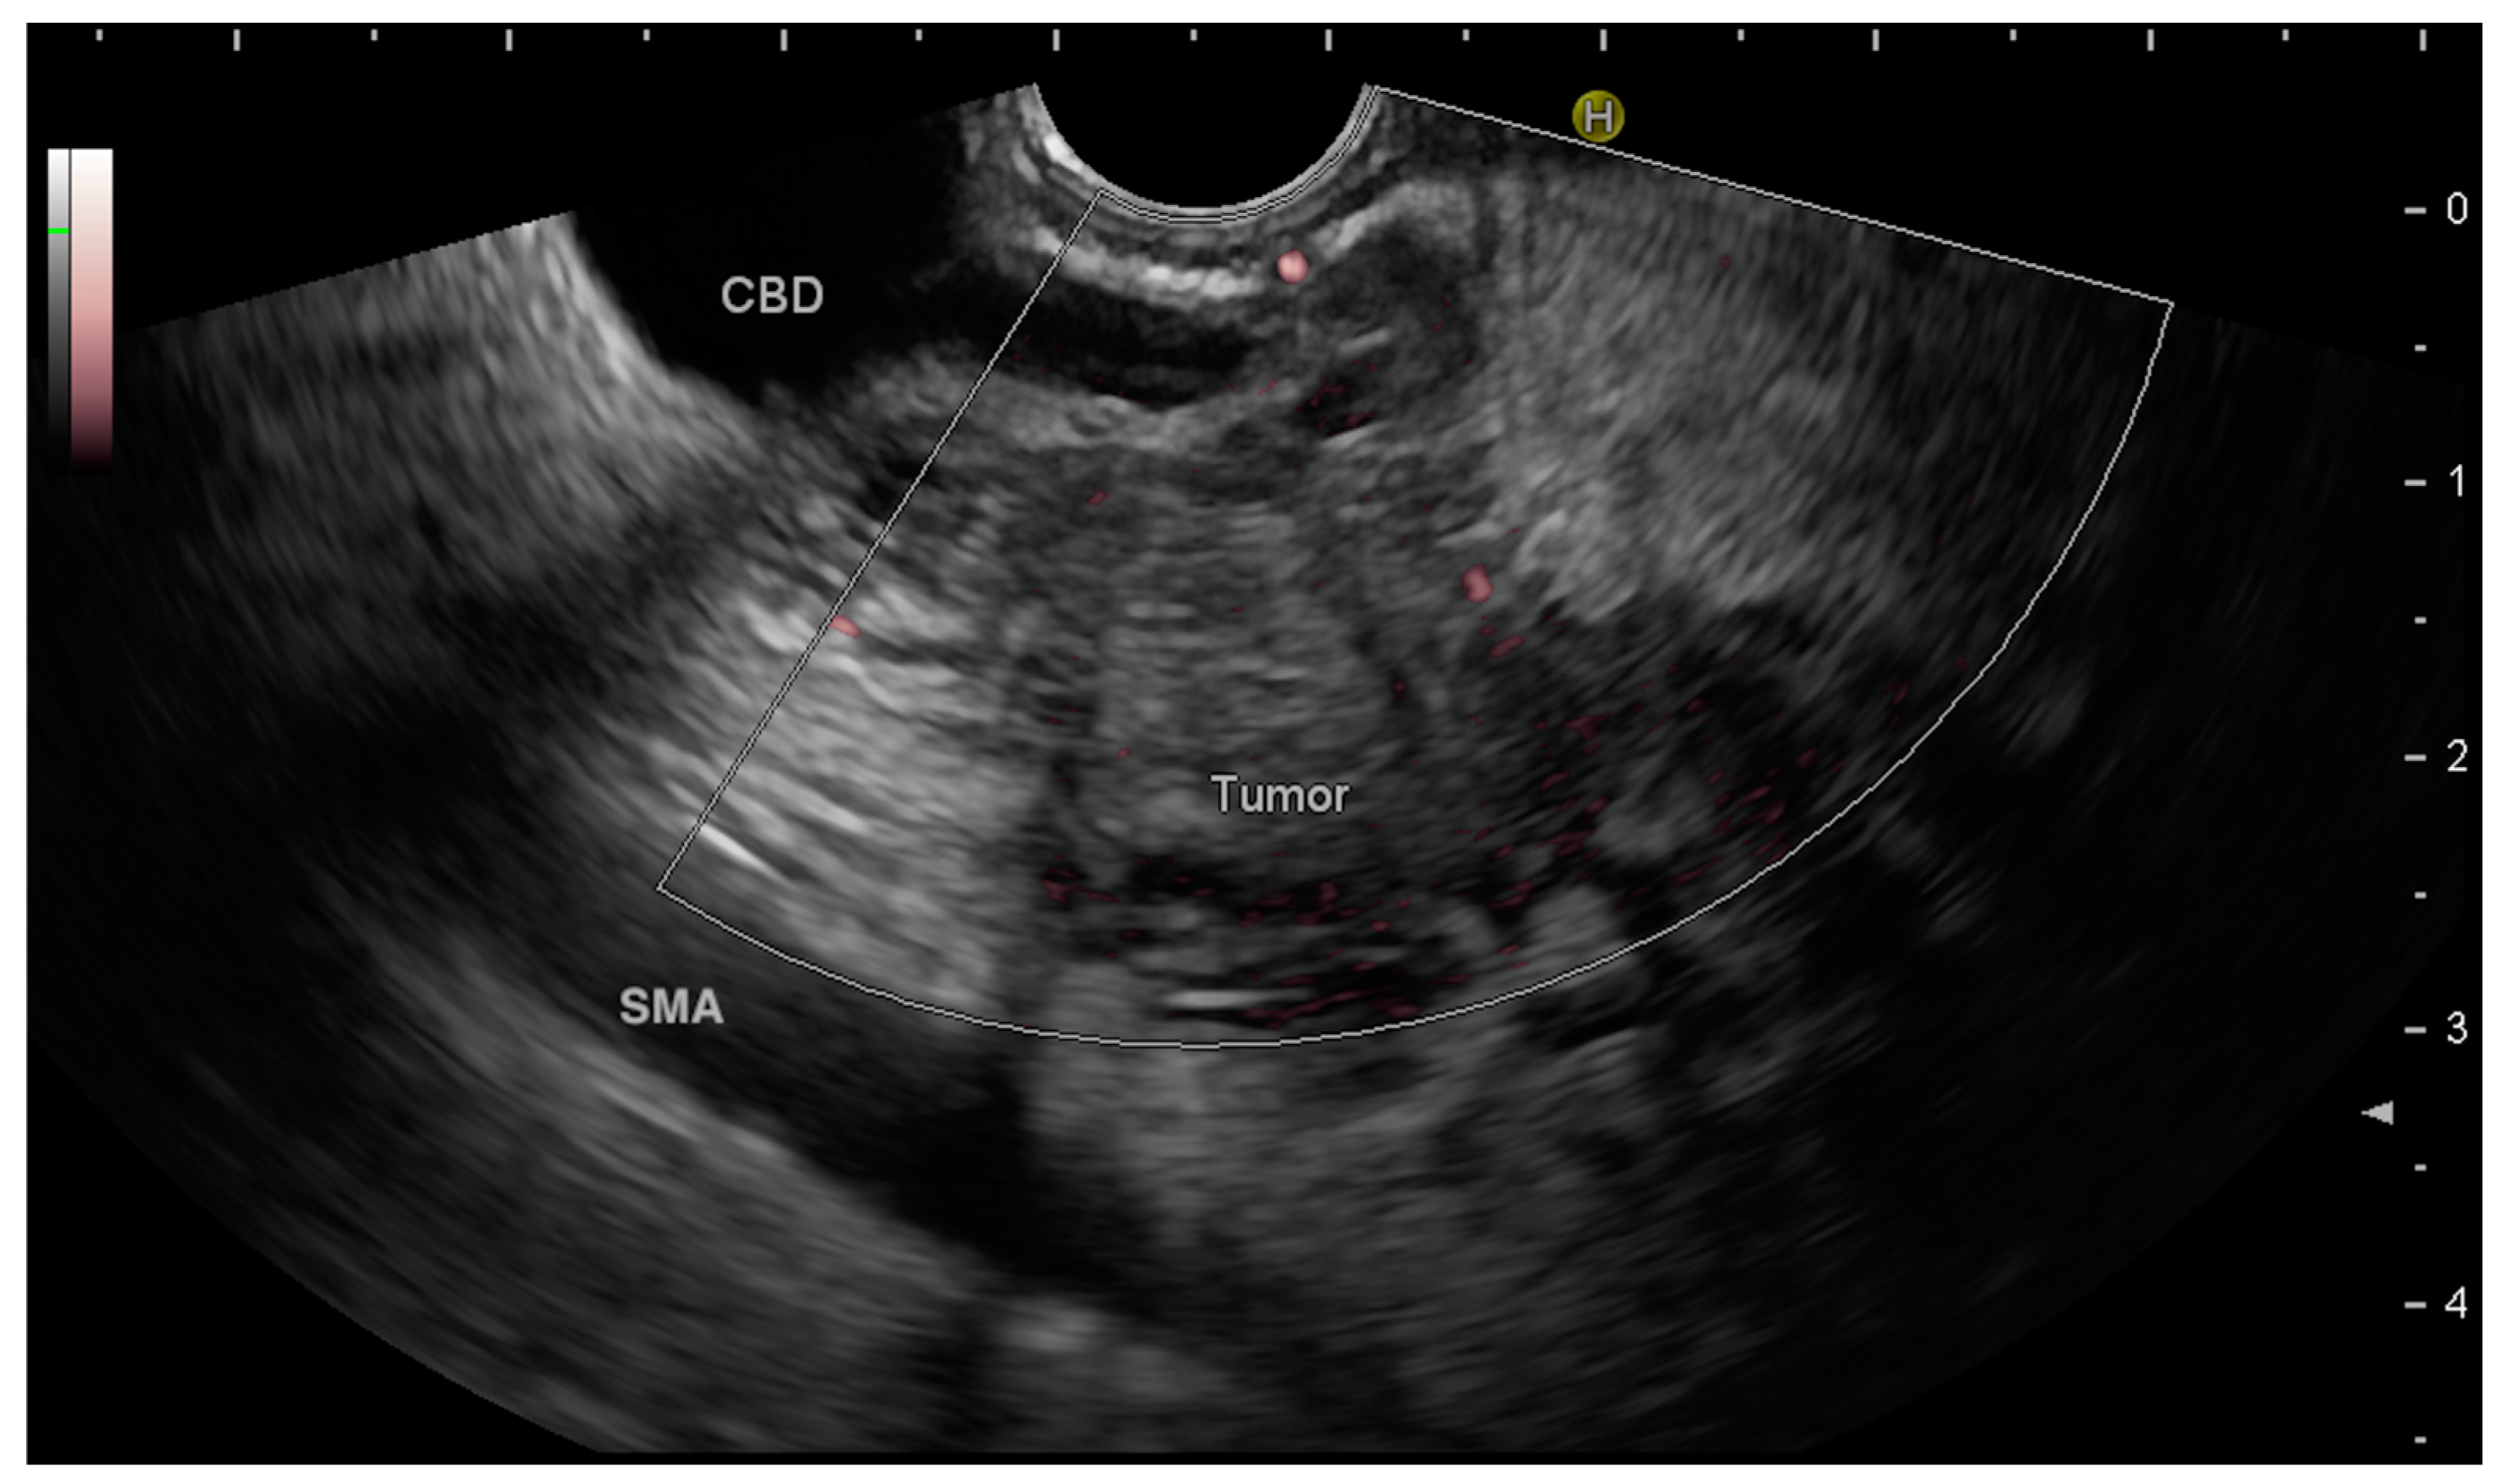

The first step is the proper description of the anatomical site where the potential mass is located. In the case of “easy” findings, where the mass is easily described by radiological imaging, EUS will confirm and describe the relationship between the mass and the surrounding anatomical structures (ducts, vessels, other organs) (Figure 1).

Figure 1.

A small hypoechoic pancreatic tumor in the head of the pancreas determines a stenosis with upstream dilation of the common bile duct (CBD). The superior mesenteric artery (SMA) is not involved in the tumor.